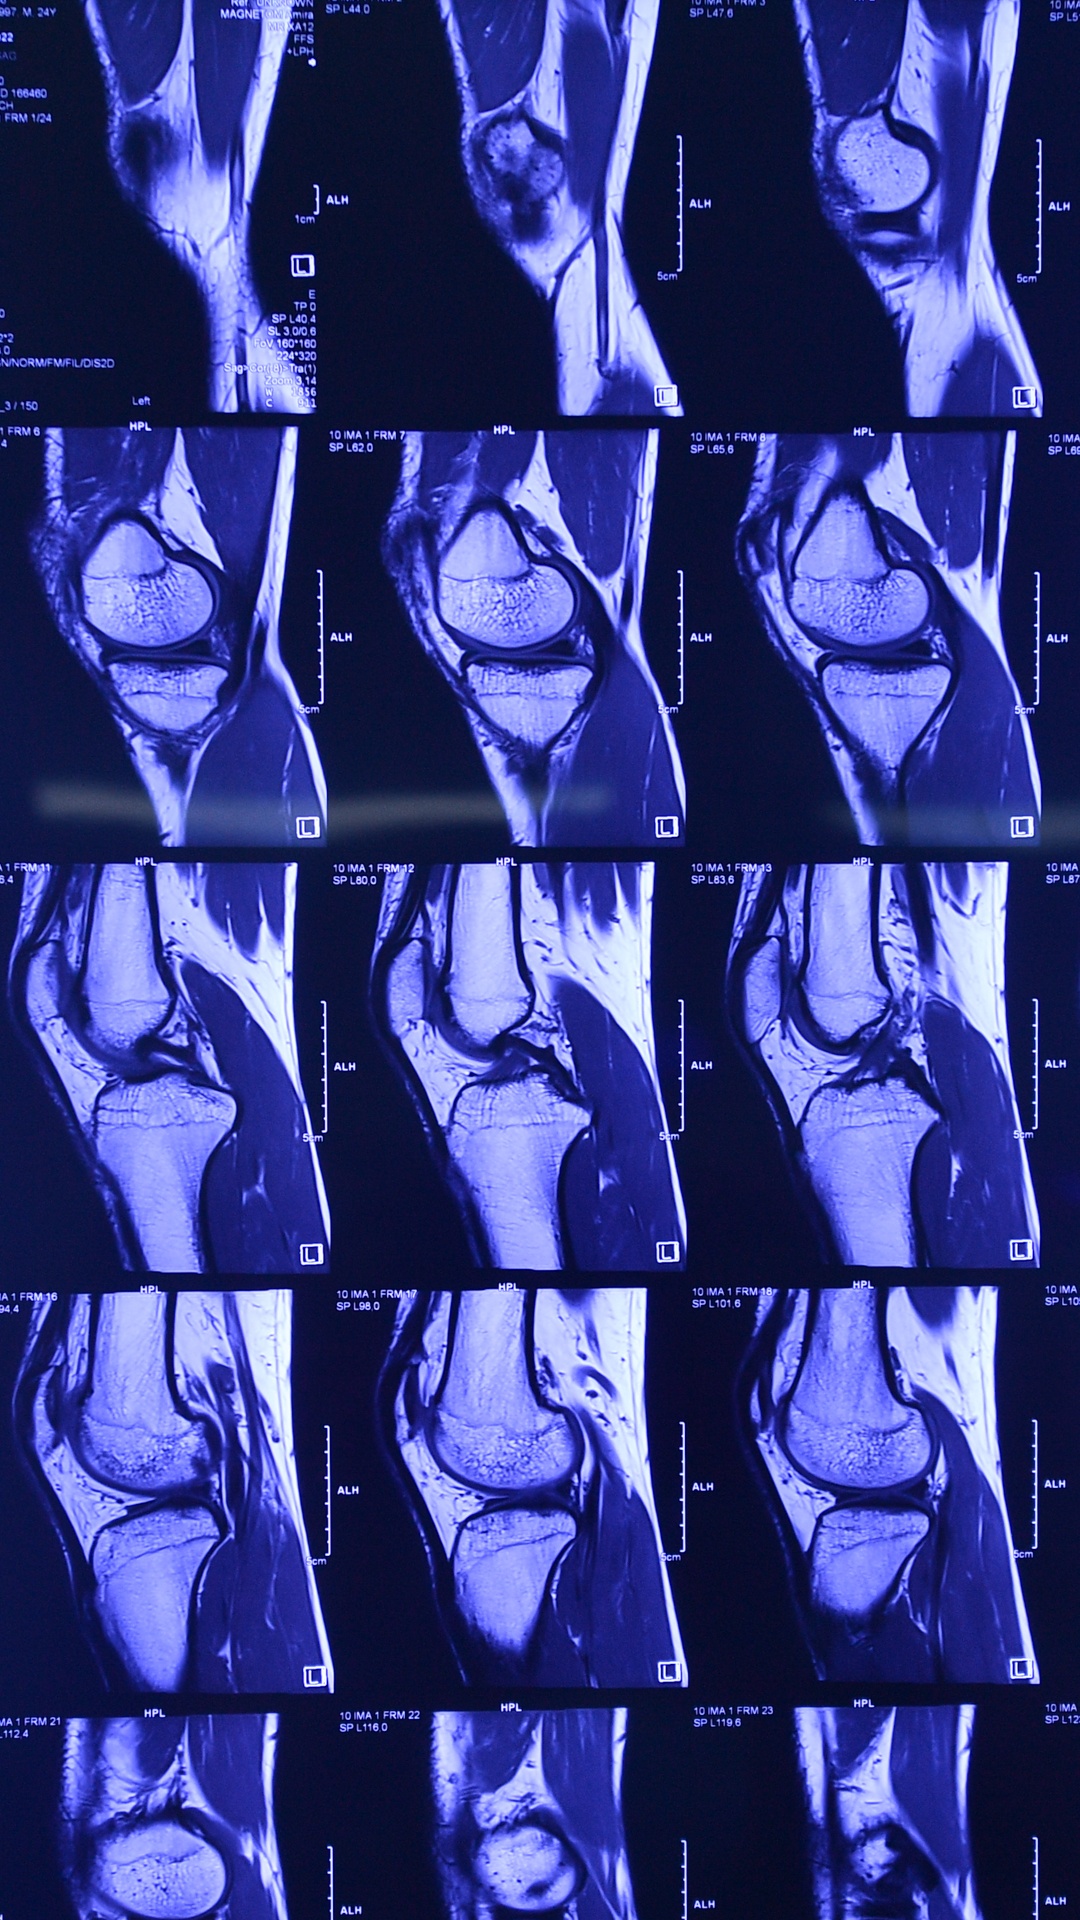

| Trong một lần tập luyện, sau pha tiếp bóng sai tư thế, tôi ngã sụp ra sân. Cảm nhận rất rõ tiếng bụp trong khớp gối, tôi chắc chắn có điều gì đó không ổn so với những chấn thương hàng ngày anh em chơi đá bóng vẫn đối mặt. Vài ngày sau, đầu gối sưng nhiều hơn, đau, không co duỗi được. Tôi đi chụp cộng hưởng từ MRI và biết mình bị đứt dây chằng chéo trước. Với một người đam mê chơi bóng mà không thể co duỗi chân, thế giới như sụp đổ trước mắt. |